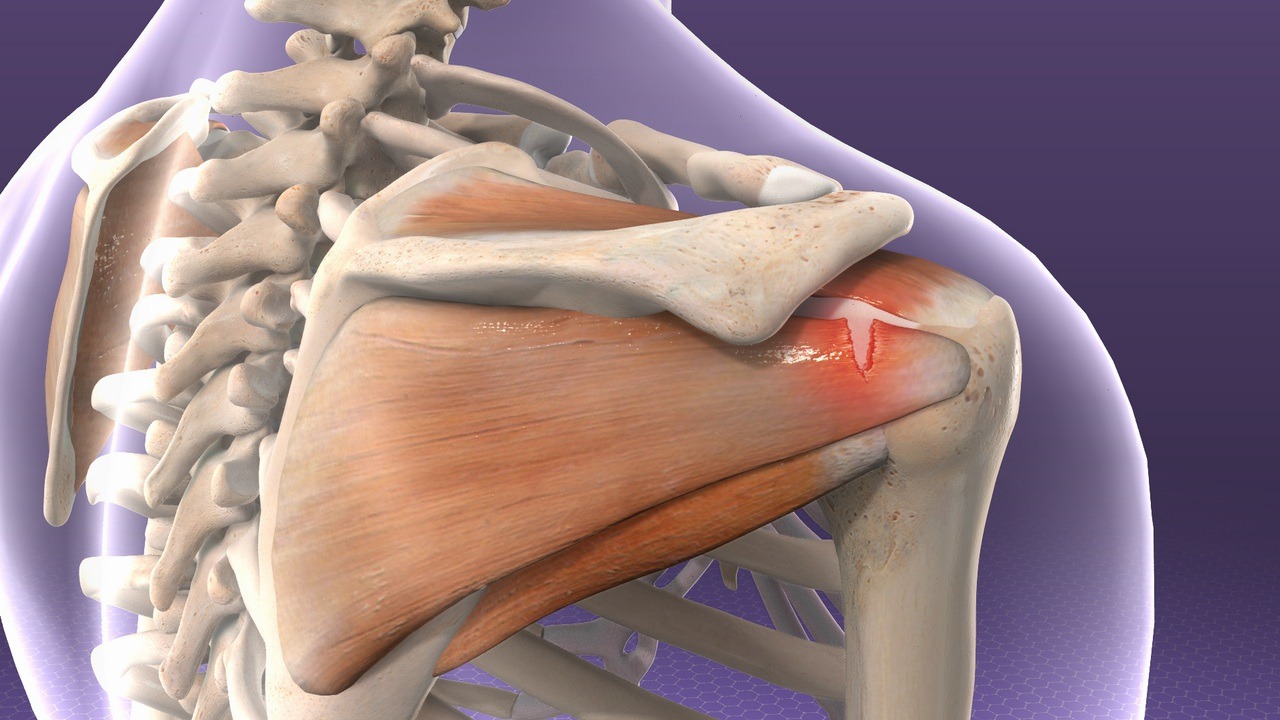

Фотографии мышц ротаторной манжеты плеча